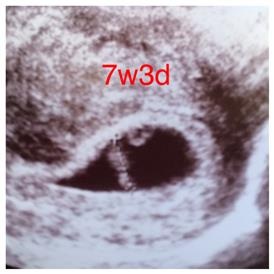

The first two with the blue writing are my son and the one with the red writing is this baby! Image Attachment(s):

Oh wow... I guess you were part of the 3% that was incorrect. In the last pic it seems like the middle but more right than left do I would say boy, but my gut says girl since you seem to be the opposite.